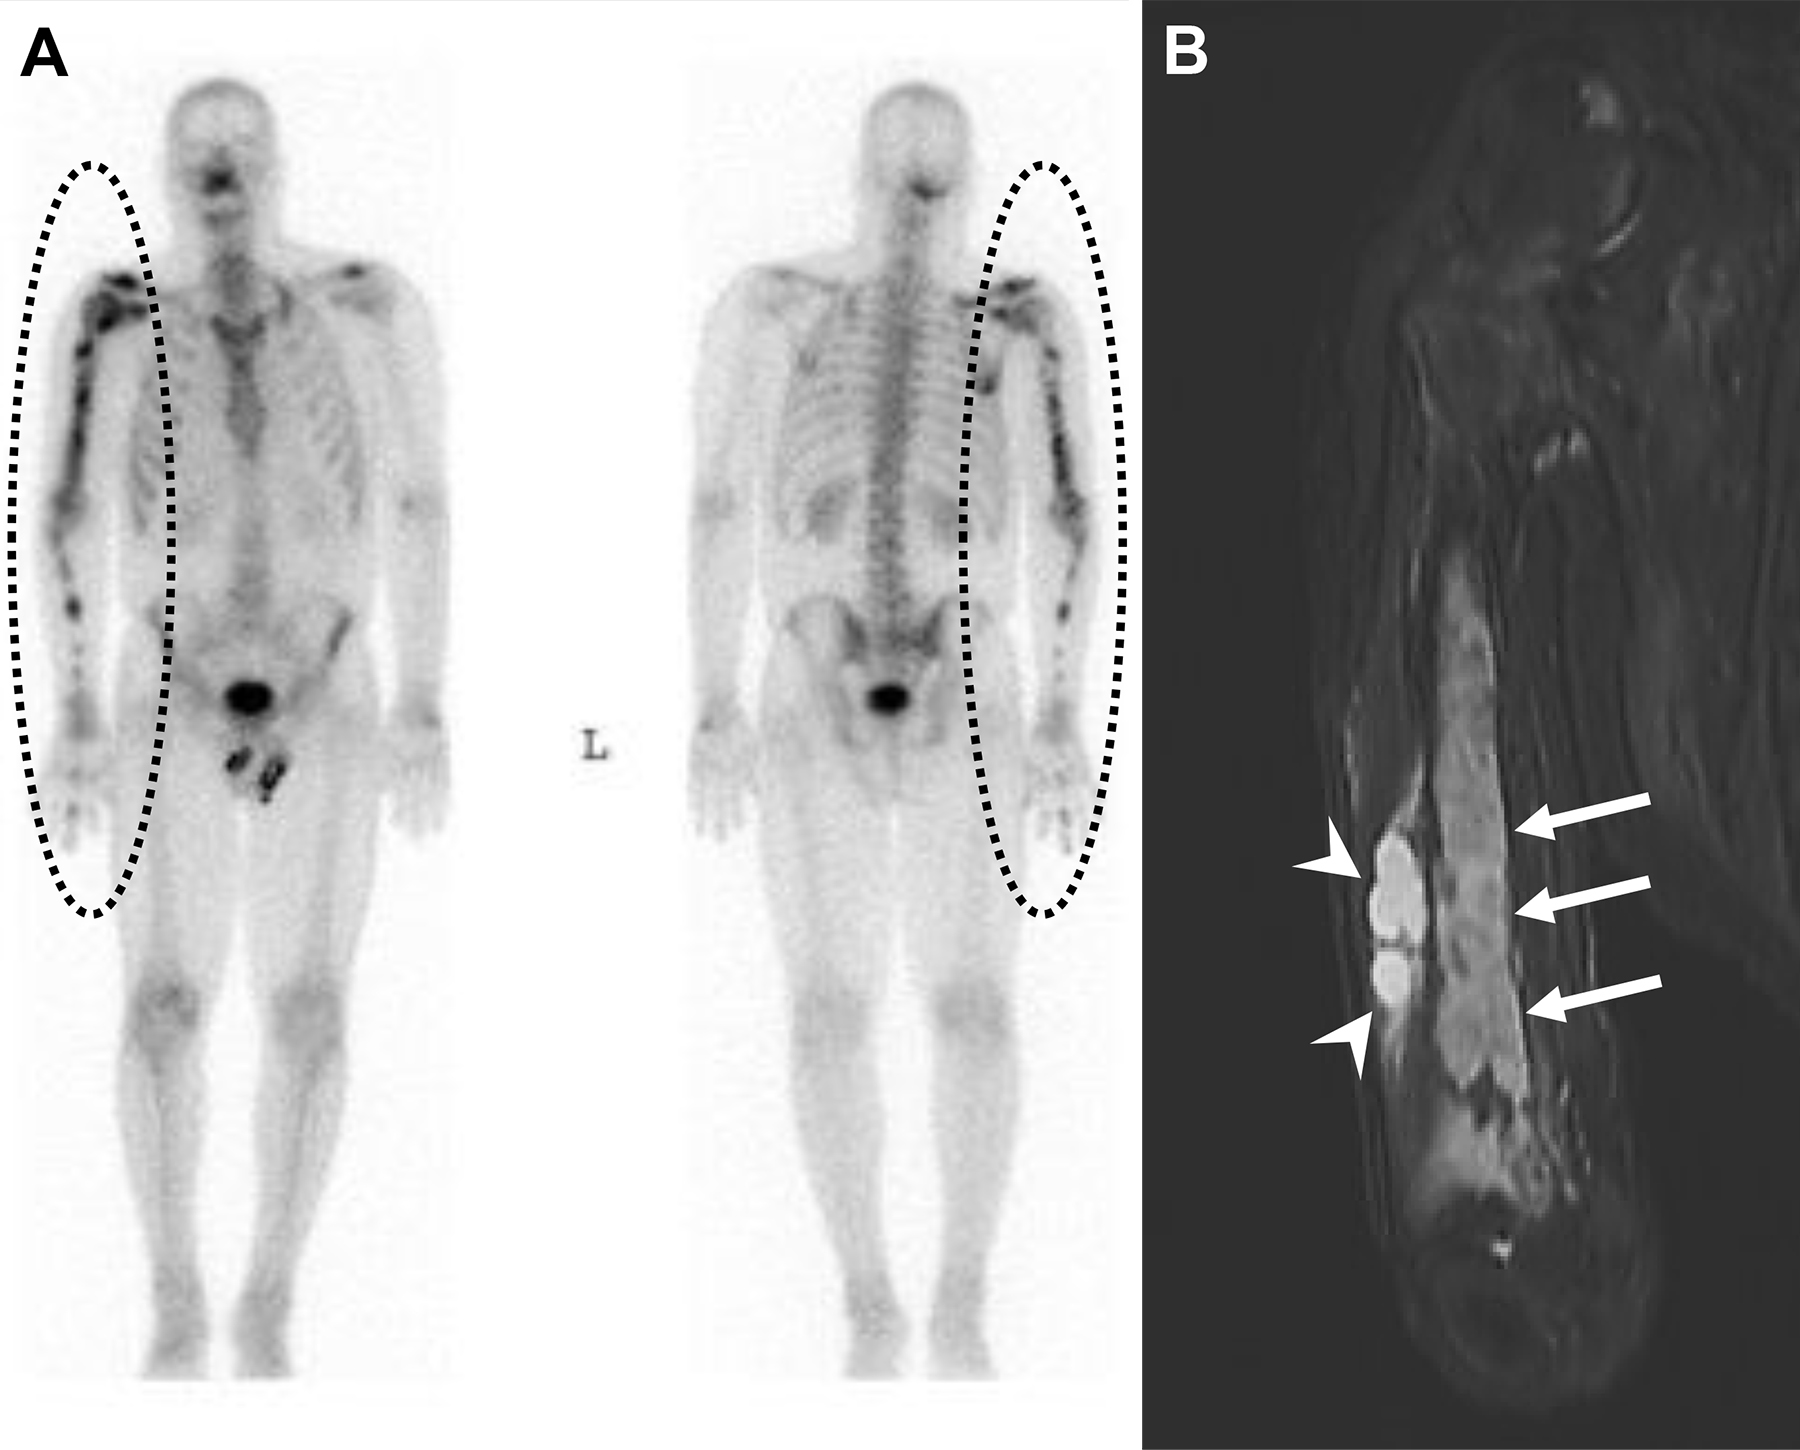

Osteoartropatia Ipertrofica (HOA) in un uomo di 56 anni con noto tumore al polmone.

L’indagine scintigrafica evidenzia una caratteristica ipercaptazione lineare corticale lungo le diafisi delle ossa lunghe tubolari (e bilateralmente a livello zigomatico). Questo pattern simmetrico e periferico è noto come segno del “binario del tram” (tram-track sign).

L’imaging tradizionale conferma la base fisiopatologica del reperto scintigrafico, mostrando una reazione periostale (apposizione di nuovo osso lamellare) a livello metadiafisario.

L’osteoartropatia ipertrofica (che in questo caso rappresenta una sindrome paraneoplastica, spesso secondaria a tumori polmonari) è caratterizzata da una classica triade clinico-radiologica: periostite diffusa delle ossa lunghe, ippocratismo digitale (dita a bacchetta di tamburo) e manifestazioni artritiche/artralgiche. La scintigrafia ossea è estremamente sensibile nell’identificare l’attività periostale in fase precoce.

Periostite indotta da voriconazolo in una donna di 62 anni con linfoma a cellule T che ha sviluppato una coccidioidomicosi polmonare.

L’esame scintigrafico evidenzia un’ipercaptazione diffusa ma asimmetrica a carico del periostio, con un pattern misto (lineare sulle ossa lunghe, a chiazze sulle coste e globulare a livello ischiatico).

La TC del torace conferma la base fisiopatologica del reperto funzionale, documentando un’intensa (“florida”) apposizione di nuovo osso periostale a carico degli archi costali destri.

La periostite indotta da voriconazolo è una complicanza scheletrica ben documentata e dolorosa che può insorgere in pazienti sottoposti a terapie prolungate con questo farmaco antifungino. Poiché il voriconazolo contiene fluoro, l’accumulo cronico può determinare una fluorosi iatrogena, stimolando un’abnorme reazione osteoblastica periostale. La scintigrafia ossea è lo strumento d’elezione per mappare l’estensione dell’interessamento scheletrico sistemico.